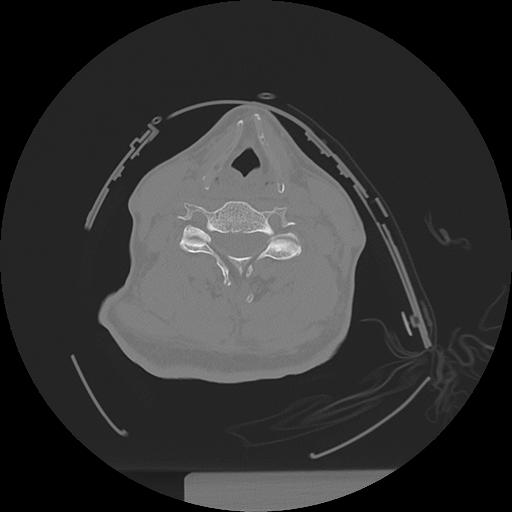

11 HUESO,,Axial,2.0,HUESO,,